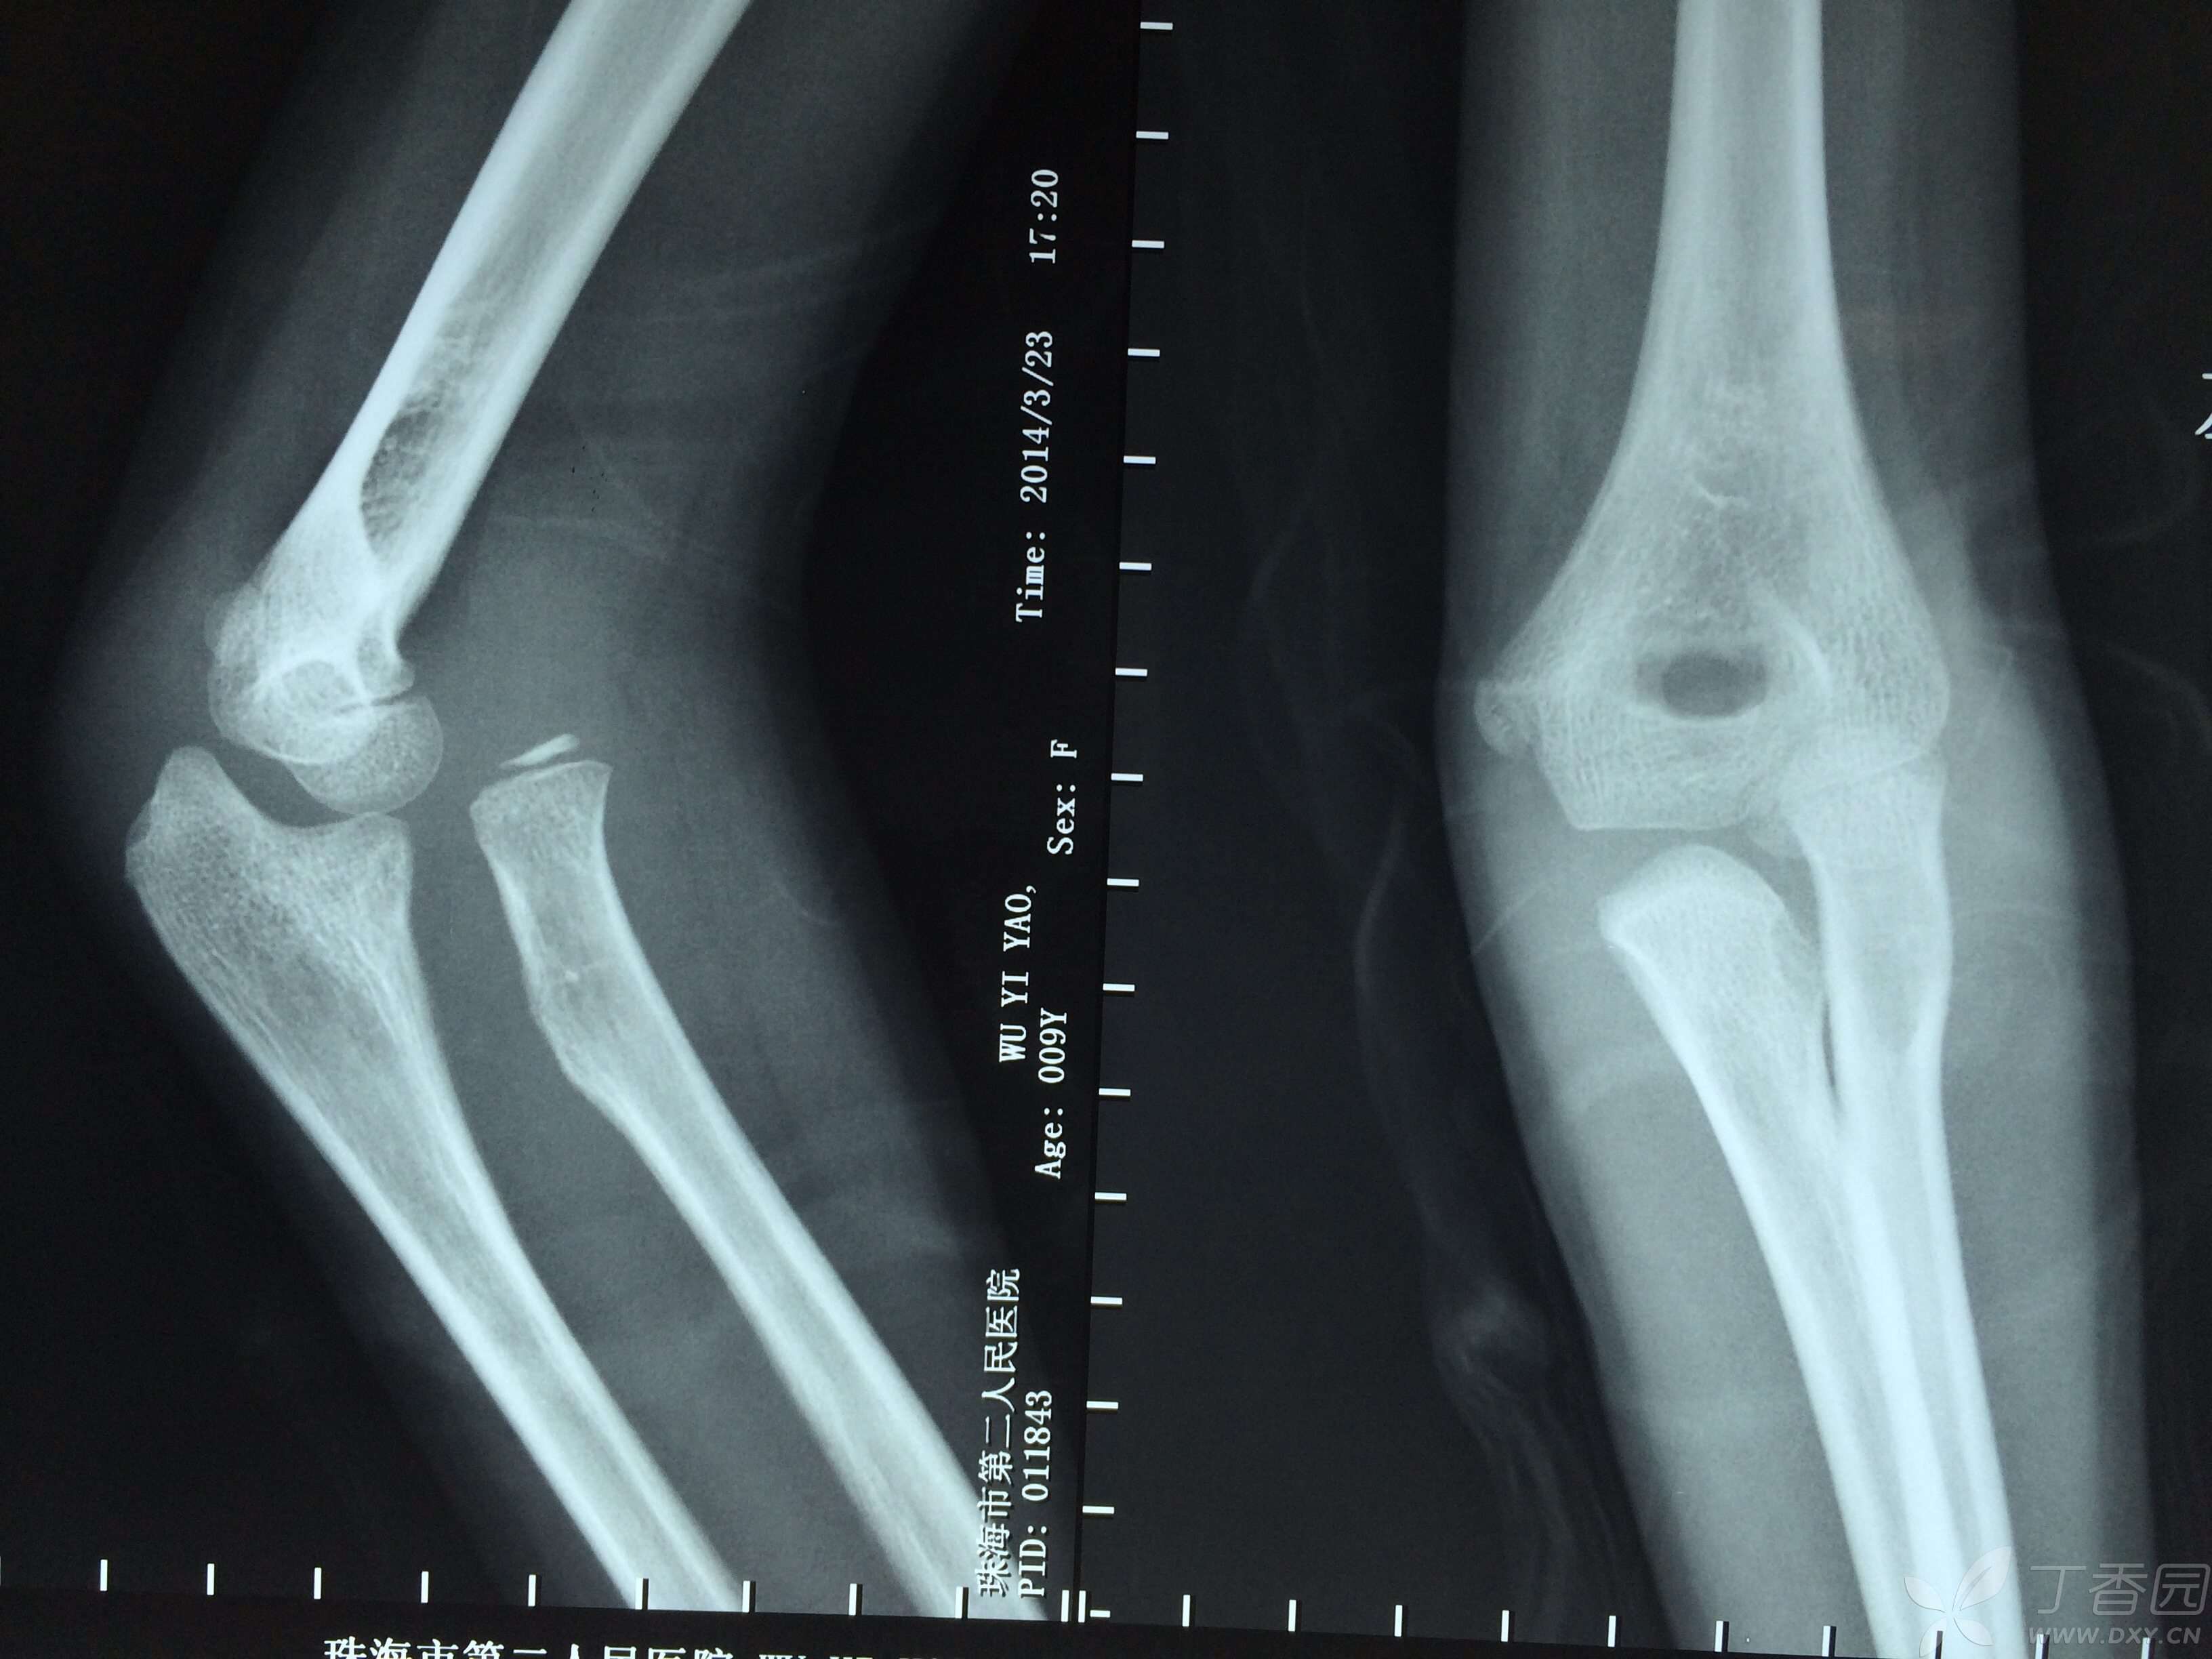

桡骨小头脱位,请求治疗方案